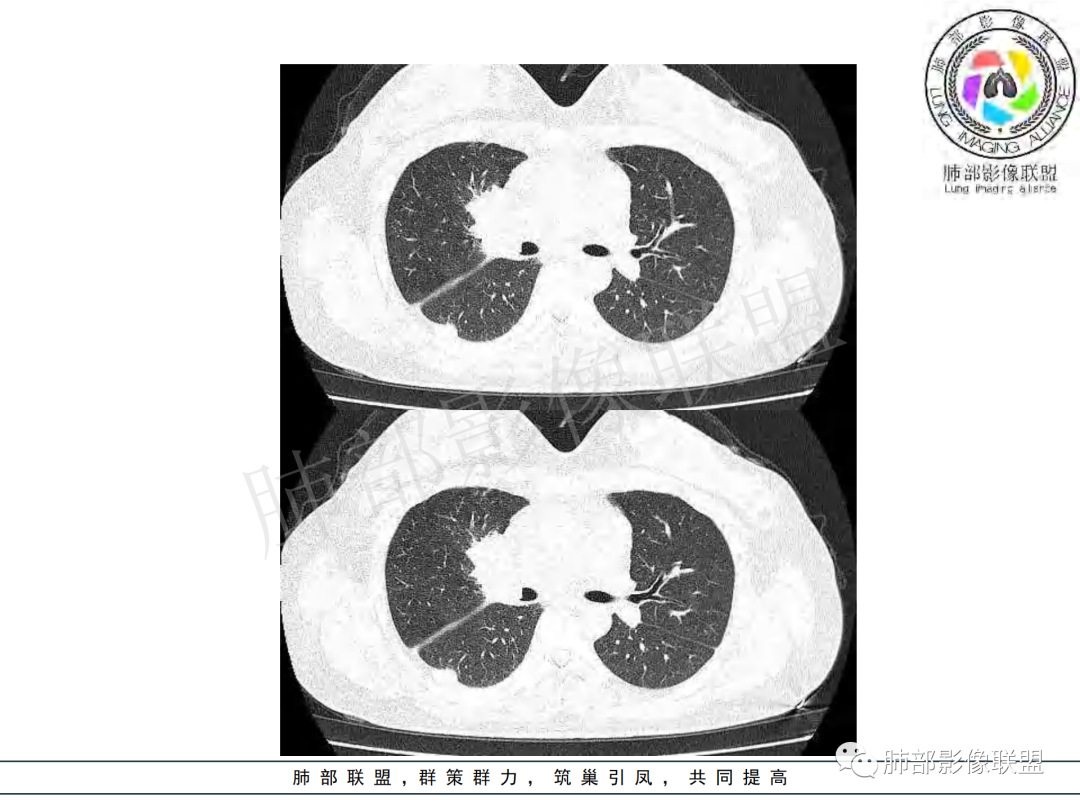

右肺肺门旁肿块,右肺中间段支气管腔内结节,增强强化不均;纵隔多发淋巴结环形强化,右侧少量胸腔积液,临床发热入院,考虑结核,鉴别肿瘤。

右肺门增大,远端花花草草不明显,支气管管壁增厚,纵隔淋巴结环形强化,年龄,病程,考虑炎性病变,结核可能,有个层面支气管截断,有强化,鉴别粘表。

纵隔多组及右侧肺门多发肿大淋巴结,部分融合,不均匀强化,内见斑片状坏死区及环状强化,后者坏死边界尚清晰,肺门区肿大淋巴结与肺组织边界不清,年轻女性,8个月病史,发热首发症状,考虑淋巴结核并向肺内侵及(破溃?),鉴别淋巴瘤

女,20,病程长达8月,发热、胸痛、右侧胸腔积液病史。胸部CT:右肺门旁不规则肿块影,右中间支气管腔内结节,纵隔多发淋巴结肿大;强化不均匀,灶性坏死灶,环形强化;右侧少量胸腔积液并局部肉芽肿样突起。年轻女性,长病程,多部位,考虑慢性炎症,结核?鉴别肿瘤。

青年,右肺门增大,见软组织肿块影,部分支气管腔结节,并管腔狭窄,增强后明显不均匀强化,伴纵隔多发肿大淋巴结,环形强化,考虑恶性,类癌,鉴别支气管内膜结核

右肺门不规则肿块,向气管腔内生长,不均匀强化,其内粘液栓,纵隔淋巴结增大,部分有坏死,胸膜结节强化,考虑恶性,粘表?类癌?鉴别结核

右肺肺门旁肿块,右肺中间段支气管腔内结节,增强强化不均;纵隔多发淋巴结环形强化,右侧少量胸腔积液,考虑结核可能,鉴别肿瘤。

年轻女性,慢性病程,发热、胸痛。右肺门旁不规则肿块影,纵隔多发淋巴结肿大;强化不均匀,环形强化;右侧少量胸腔积液;首先考虑结核,鉴别肿瘤,结节病。

女性,20岁。高热、畏寒。右肺上叶近肺门区不规则肿块,周围斑点、片小结节影伴肿大淋巴结,肿块包绕并突入右主支气管腔内,增强后肿块不均匀强化,淋巴结环形强化中心低密度,考虑结核。

本例患者,年轻女性,慢性病程,多次抗感染治疗效果不佳,实验室检查示白细胞及中性粒细胞不高,不支持普通细菌感染,虽然肺泡灌洗液X-Pert检测阴性,结合患者胸部CT结核感染亦不能排除,胸部CT主要表现为右侧肺门及纵隔淋巴结肿大,仔细观察不难发现右中间支气管内新生物凸向管腔内,增强扫描,右肺门(10R)及纵隔淋巴结(2R,4R)明显不均匀强化,内部呈不规则低密度无强化区,被周边高强化区包绕(环形强化)的特点,首先应当想到纵隔淋巴结结核诊断。淋巴结分布亦不符合肺部恶性肿瘤迁徙途径。